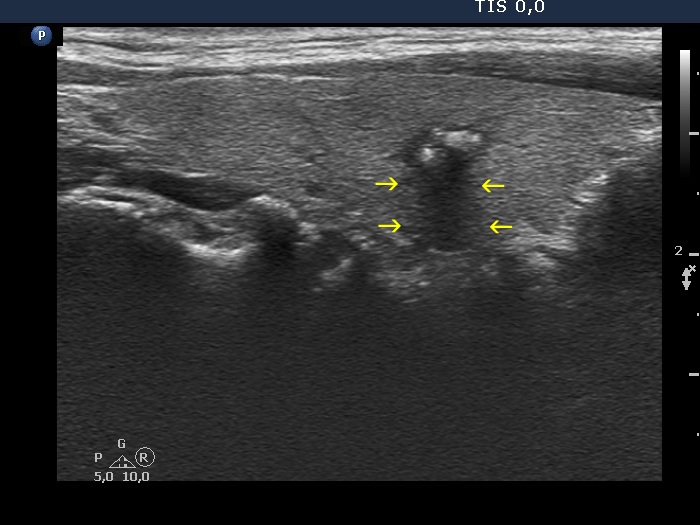

Benign lesion (cytology) - case 2019

Transverse scan

Longitudinal scan

The borders between the nodular area and the non-nodular part of the lobe are indistinctive. The cause of the blur is non-pathological in the ventral part of the nodule (yellow arrows), it can be simply explained by the similar echo structure of the neighboring tissues. On the other hand, the area marked with red arrows should be considered as pathological blur.